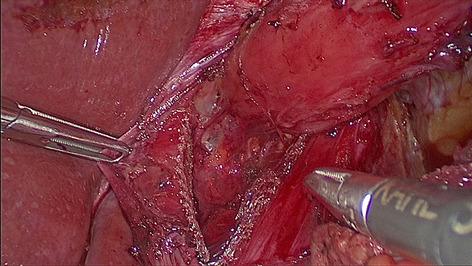

Methods: Starting 01/2019, we implemented a standardized robotic anastomotic technique using a circular stapler and ICG (indocyanine green) for our RAMIE cases at our academic center (Fig. 1). Video material of standardized RAMIE cases was recorded and criteria for selection of suitable videos for annotation were defined. Those included high video quality and performance of a standardized anastomotic phase. Anastomotic phase was defined to begin when the cautery hook touches the esophagus, and the esophagus is divided. Next a monofilament purse string suture is performed robotically. One 12-mm assistant trocar is then removed, and this incision is extended to a mini thoracotomy with a standardized length of 7 cm. The stapler head is inserted and sutured into the esophageal stump using the prepared purse string suture using the robotic instruments. Its end was defined as when the circular stapler head is successfully sutured in and the needle is cut off. Next, video annotation was performed using pixel annotation for tool identification and vector annotation for identification of instrument direction and head of the used instrument (Figs. 2 and 3).

Results: Since 01/2019 a total of 94 RAMIE cases were performed, all cases were set up to be recorded. Successful and complete video recording was found in 60% of cases. N = 15 videos were evaluated for video annotation. 60% (n = 9 videos) were found suitable for annotation as defined above. Reasons for exclusion were failure of standardization of the anastomotic phase such as change of circular stapler size, additional lymphadenectomy, additional swap in the picture, rupture of suture, incomplete video or minor bleeding. Mean time of the anastomotic phase was 27.39 min (range 22.03 min- 30.97 min). The robotically performed part of the anastomotic phase showed a mean of 18.19 min, compared to a mean of. 9.2 min of mini-thoracotomy and stapler head introduction. This leads to a total of 163.72 min of video data suitable for annotation. Interestingly, annotation was found to be more time consuming than previously published as 4 instruments were actively used compared to 2 for e.g. in robotic urological surgery. An average of 6 min per picture were found for pixel annotation, compared to 3 min for vector annotation.